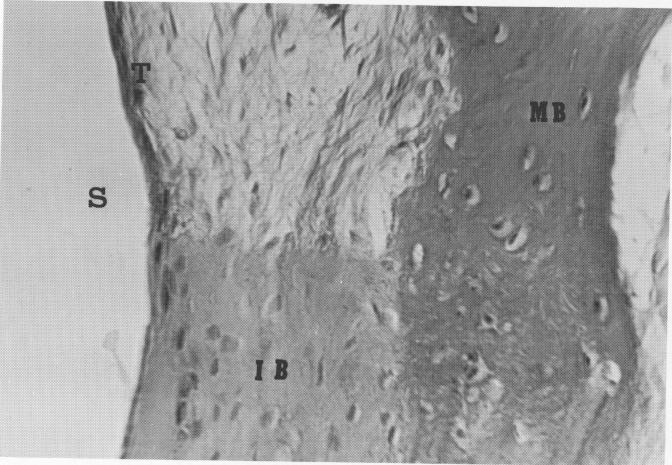

Fig. 4-101. Magnification of box in Fig. 4-100. Upon magnification of the bone over the lingual frame site (S), its character becomes clearer. There is mature bone (MB) separated from the implant site by typical connective tissue (T), and immature bone contacting the implant site (IB). (From Bodine, R. L., Jr., and Mohammed, C. I.: Histologic studies of a human mandible supporting an implant denture, J. Prosth. Dent. 21: [2] :203-216, 1969.)